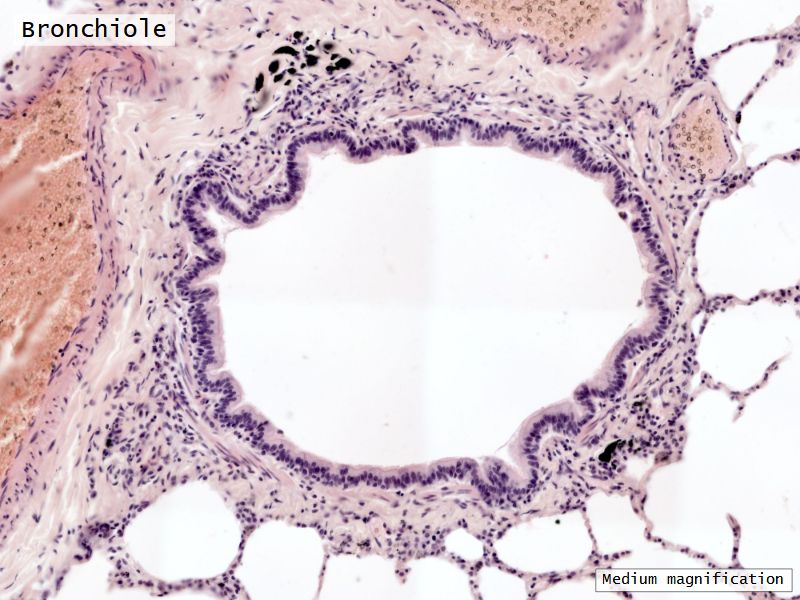

Respiratory epithelium

• Pseudostratified

• Ciliated

• Columnar

• Epithelium with

• 4 Cells

• Ciliated columnar cells

• Non-ciliated columnar cells

• Goblet cells

• Basal cells